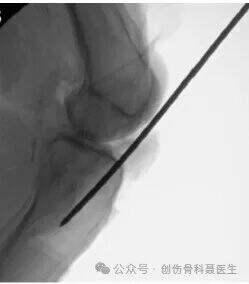

Sidovisning: På en standard lateral radiografi (där femoralkondylerna och tibialplattorna överlappar varandra) ligger införingspunkten vid "vatten-skiljelinjen" – samsättningen (övergångszonen) mellan den anterioara randen av tibialplattan och början av tibiaskaftet.

Standard lateral radiografi:

På en korrekt lateral bild bör den mediala och den laterala femoralkondylen i princip överlappa varandra, och den mediala och den laterala tibialplattan bör också överlappa varandra. I denna verkliga lateralprojektion bekräftas att införingspunkten ligger vid vatten-skiljelinjen (samsättningen mellan plattan och skaftet).